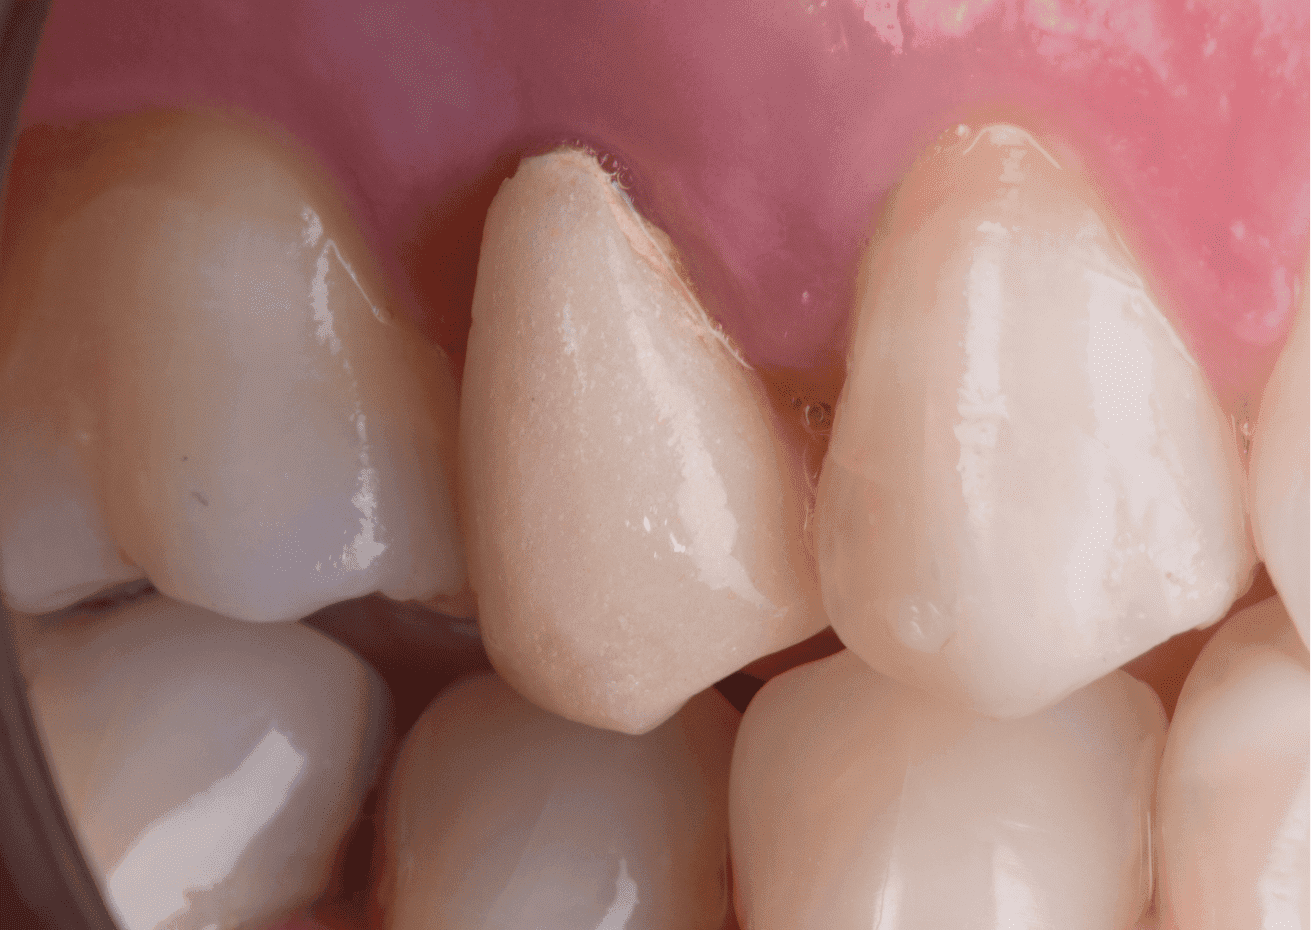

A restauração final foi realizada utilizando scanner digital e coroa em resina vitrocerâmica BRAVA Block usinada em CAD-CAM, também foi cimentada com cimento resinoso dual Allcem CORE.

O resultado final mostra recuperação estético-funcional satisfatória com alto grau de satisfação da paciente.